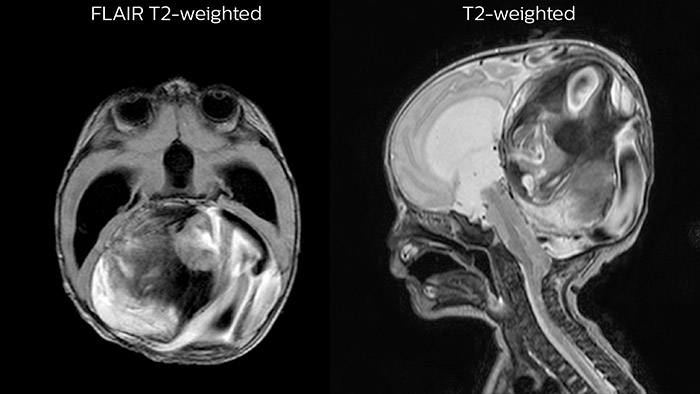

Dural sinus malformation (DSM) Initial examination

After three times of coiling and acryl based embolization